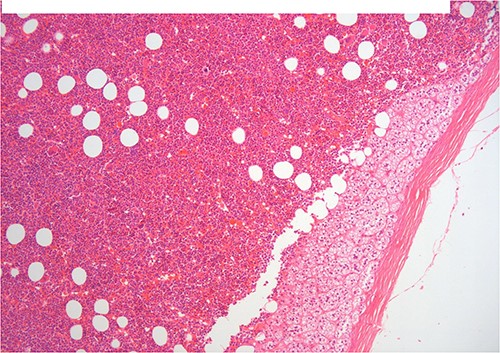

A 50-year-old woman was referred for surgical resection of a large right adrenal mass, which was incidentally found in an ultrasound scan performed for vague abdominal symptoms. Subsequently an abdominal MRI scan depicted a 16 × 15 × 6 cm right adrenal mass with characteristics suggestive of a myelolipoma, without evidence of vascular or periadrenal organ invasion (Figs 1 and 2). The patient underwent a comprehensive hormonal serum testing that confirmed a nonfunctioning adrenal mass. Because of the size of the lesion, an open operative approach was selected. Through a supraumbilical midline incision the mass was carefully dissected from the surrounding structures. It was adherent to the right kidney, the liver and the inferior vena cava without, however, compressing it. The harmonic scalper was used and clipping of the adrenal vasculature as appropriate. Intraoperatively, there was no adverse event. The specimen was removed intact and was sent for histological examination (Fig. 3). A silastic corrugated drain was inserted before closure of the laparotomy. The patient’s postoperative course was unremarkable and she was discharged on the third postoperative day. Histopathology revealed a lesion consisting predominantly of fatty tissue containing all types of hematopoietic stem cells and confirmed the diagnosis of myelolipoma (Figs 4 and 5).

H–E ×200 hematopoietic elements including megakaryocytes with some lipocytes. Above there is a rim of compressed adrenal cortical tissue and fibrous capsule of the adrenal.

On histopathologic examination, myelolipomas are predominantly composed of mature adipose tissue with interspersed hematopoietic tissue components. These fatty elements and hematopoietic areas may be clearly separated, or they are often intermixed.